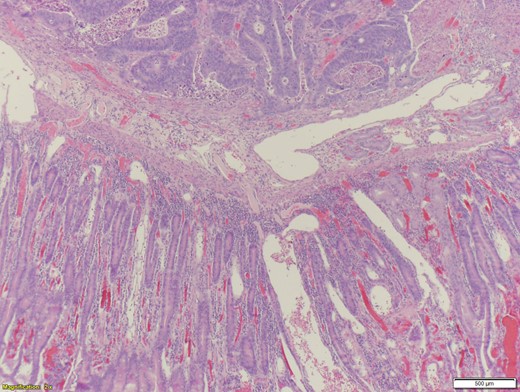

A 70-year-old female presented to the emergency department with complaints of diarrhea, vague, dull abdominal pain, unintentional weight loss and poor appetite. No hematochezia or melaena stated. Fecal occult is strongly positive in the ED. No endoscopies were found in her records. PMHx included COPD, osteoarthritis and DVT. Significant physical exam findings included mild, diffuse abdominal tenderness and RUQ palpable mass, and normal bowel sounds. Labs were significant for a hemoglobin of 5.7, hematocrit of 18.6% and CEA of 29.6. An abdominal/pelvis CT exhibited a 6 cm circumferential mass of the hepatic flexure (Figs 1–3). Two days later, a right hemicolectomy with en bloc pancreaticoduodenectomy was performed. Pathology showed adenocarcinoma stage IIIc (Figs 4–10). Post-operatively, an abdominal/pelvis CT showed bilateral pulmonary emboli and a 14 cm pelvic abscess. Bilateral lower extremity ultrasound showed low probability for DVT. Exploratory laparotomy was performed where the pelvic abscess was seen and extensive lysis of adhesions, resection of ileocolonic anastomosis for contained leak and ileostomy performed. Approximately 4 months after discharge, the patient passed away while in a long-term care facility.